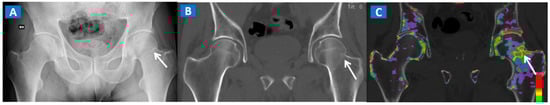

Figure 4.

A 61-year-old female with non-displaced fractures of the right iliac and pubic bones. On the standard coronal 1 mm CT images (A,B) the iliac fracture is well depicted (arrow in (A)), whereas the pubic fractures could be easily missed (arrow in (B)). The presence of BME on the corresponding 1 mm coronal reconstructed DECT images (C,D) confirms the non-displaced fractures. The 3D coronal DECT map (E) yields a clear picture, depicting the fractures of the right side and ruling out the presence of BME on the left side.